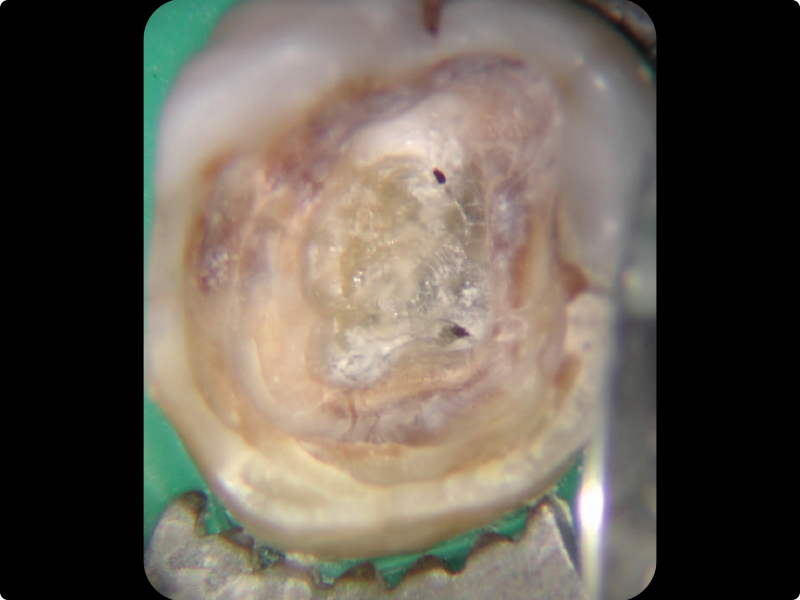

• Endodontic retreatment: why, when, and how to retreat.

• Redefining a proper access cavity.

• Removal of intracanal retainers: metal posts, fiber posts, zirconia posts.

• Removal of root canal filling materials.

• Retreatment of the teeth filled in the previous practical session.